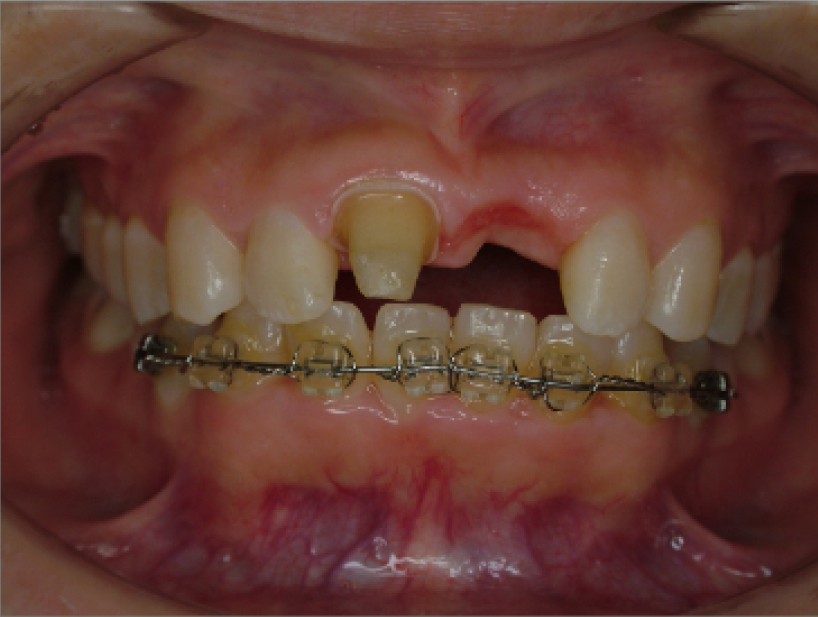

治療前治療後

| 治療内容 | 前歯インプラント治療/下前歯矯正治療 |

|---|---|

| 患者様の年齢 | 19歳 |

| 患者様の性別 | 女性 |

| 治療期間 | 1年 |

| 治療回数 | 矯正治療合わせて45回程度 |

| 治療費用 | インプラント治療50万円/矯正15万円 |